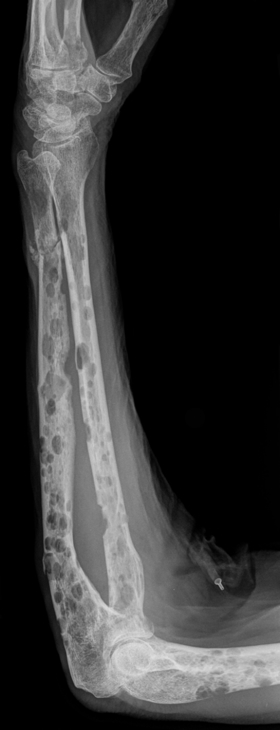

- Skeletal survey or CT/MRI: Lytic bone lesions

- Plasma cells activate osteoclasts → bone resorption → lytic lesions + hypercalcaemia

- Pathological fractures

- Bone lesions